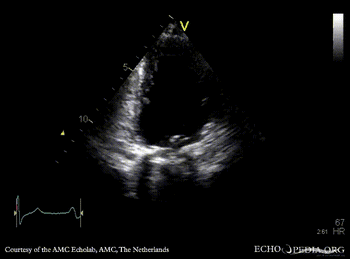

Mechanical mitral valve prosthesis

Courtesy of: AMC Echolab, AMC, The Netherlands

A4CH A2CH